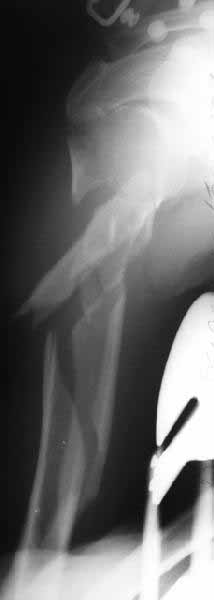

It is very difficult to comment meaningfully without knowing whether or not the proximal humerus is involved and to what extent. There must be some sort of radiograph that shows the proximal humerus better.

Alex The views you now show

demonstrate an extra articular fracture with good alignment on the AP, and some displacement on the lateral. This should be able to be managed with adjustment of the traction. Ilizarov is probably the best fixation if you decide to do so. However, it will heal with nonoperative treatment, with painless, reasonable function. Even if it does not heal primarily, the pieces will heal enough to become a single level problem, readily solved with compression plating.